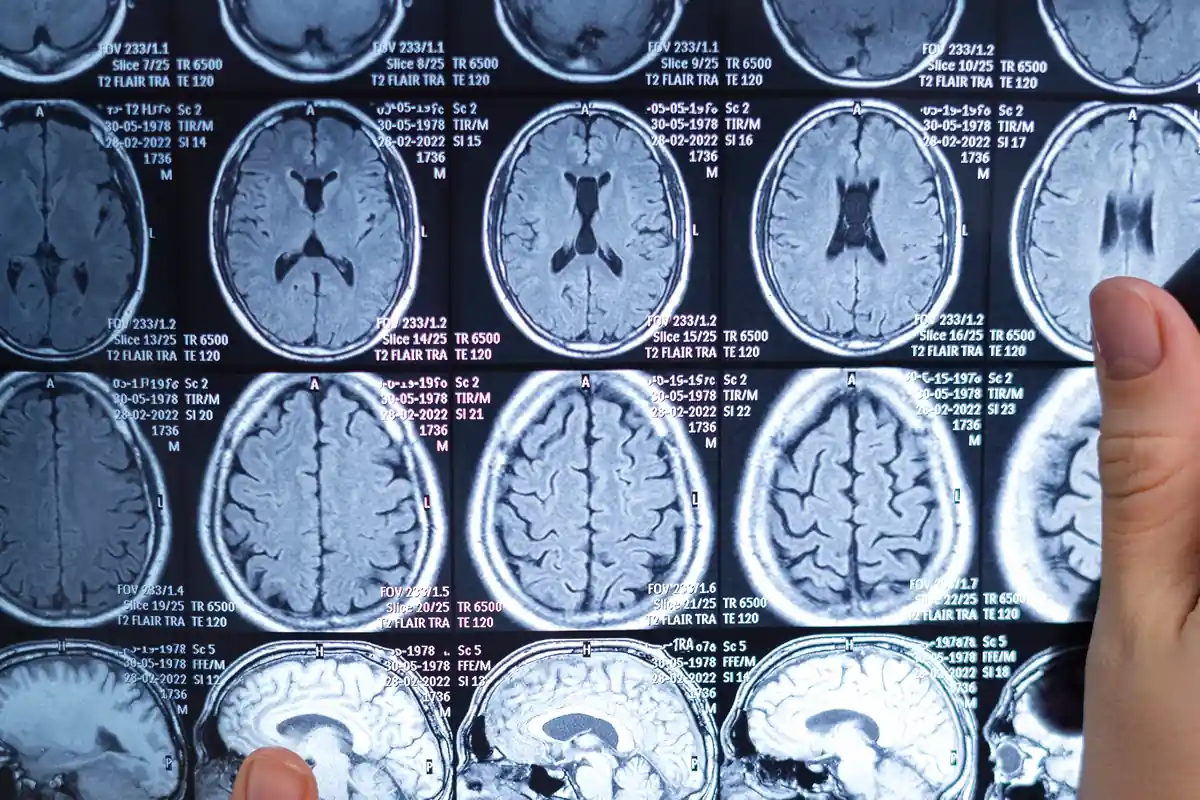

Il danno cerebrale grave è una delle conseguenze di questa malattia. Ciò accade perché, per compensare la perdita di flusso sanguigno causata dal restringimento dei vasi, si forma un’altra rete vascolare, ma incapace di soddisfare la domanda che i vasi originari coprivano. Conoscere l’anamnesi del paziente affetto da malattia di Moyamoya è essenziale per prevenire gravi complicazioni mediche. RM, TAC e SPECT sono esami diagnostici utili per valutare i danni ai vasi sanguigni.

La perdita dell’udito o della vista, mal di testa e crisi epilettiche sono alcuni dei sintomi provocati da questo disturbo. Gli angiomi cavernosi possono iniziare a sanguinare, causando sintomi simili a quelli di un ictus. I medici li diagnosticano mediante risonanza magnetica, poiché questo gruppo di vasi non è visibile nelle angiografie standard. Per questo motivo, i pazienti non possono essere sottoposti a chirurgia endovascolare con catetere. La gravità della patologia dipende dal grado di sanguinamento.

Questa malattia viene diagnosticata attraverso un esame del sangue che rileva la presenza dell’anticorpo anti β2-glicoproteina I, degli anticorpi anticardiolipina e dell’anticoagulante lupico. Una risonanza magnetica e una tomografia computerizzata aiuteranno a individuare la parte colpita e i danni provocati.